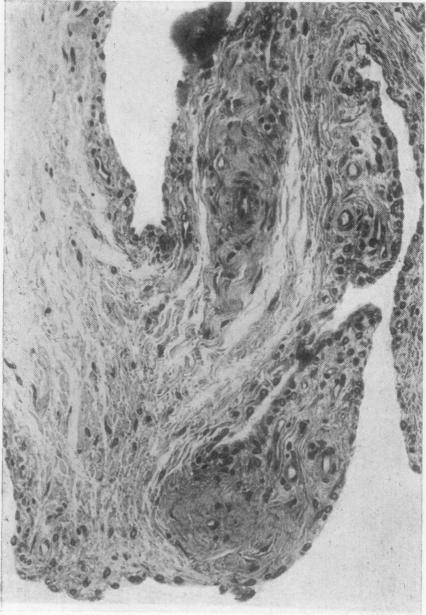

Seventeen rabbits were immunized with complete Freund's adjuvant and bovine serum albumin by the method of Dumonde and Glynn (1962), as modified by Cooke and Jasin (1972). Fifteen weeks after allergic arthritis developed in the knee joint, 8 animals were given an injection of 20 muCi yttrium 90 (90Y) into the left joint cavity; 7 were injected with 400 muCi. The animals were sacrificed at 2, 4, 8, 12, and 16 weeks and at 6 and 12 months after the injection. The right knee joint served as control for assessment of untreated allergic arthritis. Morphological control of the severity of the arthritis was provided by sacrificing 2 uninjected animals 13 weeks after immunization.

按照杜蒙德和格林(1962年)的方法,并经库克和贾辛(1972年)改良,用完全弗氏佐剂和牛血清白蛋白对17只兔子进行免疫。膝关节出现过敏性关节炎15周后,给8只动物的左关节腔内注射20微居里钇90(90Y);7只动物注射400微居里。在注射后2周、4周、8周、12周、16周以及6个月和12个月处死这些动物。右膝关节作为评估未经治疗的过敏性关节炎的对照。在免疫13周后处死2只未注射的动物,以提供关节炎严重程度的形态学对照。